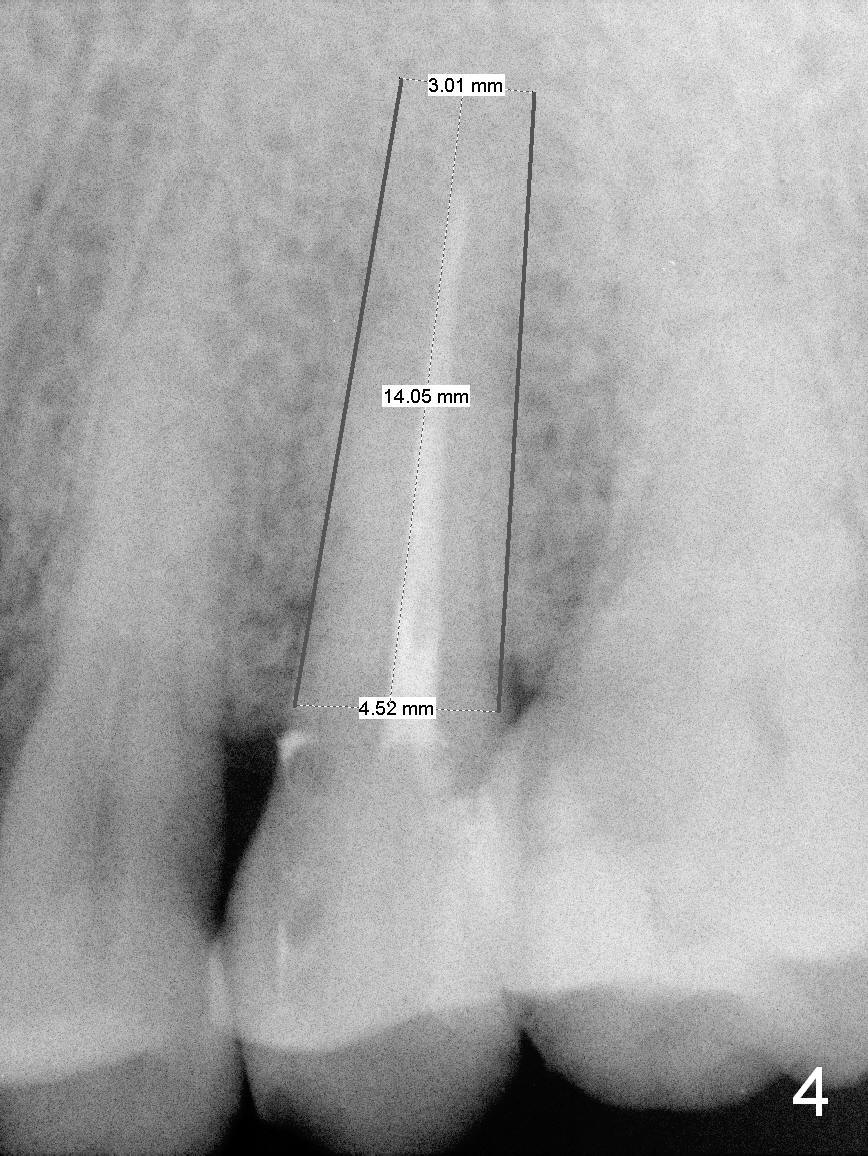

A 48-year-old man (CM) finished root canal therapy for the tooth #13 2.5 years ago (Fig.1). The tooth fractured lately (Fig.2). In spite of the fact that there is no periapical radiolucency in the most recent PA (Fig.3), the socket will be treated with No Antibiotic. Osteotomy is initiated at the junction of the lower and middle thirds of the palatal wall. The palatal cusp subgingival fracture may cause bone resorption in the palatal wall (at the crest). A 14 (Fig.4) or 13.5 (Fig.5) mm bone-level implant is probably going to have 8 mm contact with new bone.